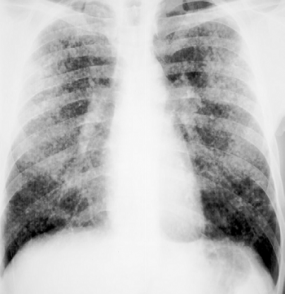

A B Reader is a physician certified by the National Institute for Occupational Safety and Health (NIOSH) as demonstrating proficiency in classifying radiographs of the pneumoconioses.

- B Readers participate in medical surveillance programs that utilize chest radiographs for the early detection of pneumoconiosis in dust exposed workers. This provides an opportunity for early interventions to minimize the chance of disease progression.

- B Readers are provided the opportunity to learn the International Labour Office (ILO) International Classification of Radiographs of Pneumoconioses classification system, the most widely used standardized procedure to document radiographic findings found in pneumoconiosis.

- B Readers get certified by an examination documenting their ability to use the ILO classification system to evaluate (classify) chest radiographs.